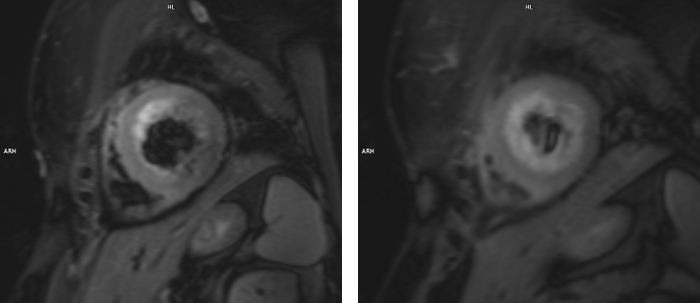

Examinarea IRM evidențiază formă tipică a ventriculului stâng care e balonizat, cu edem miocardic de la nivelul cavitații medii până la apex (examinarea cardiacă prin rezonanță magnetică este singura modalitate de a evidenția „in vivo” edemul miocardic) și, în mod caracteristic, fără priză de contrast ceea ce sugerează lipsa ariilor de necroză miocardică.

Cardiomiopatia de stress este un sindrom coronarian acut care, de cele mai multe ori, se vindecă fără sechele; examinarea cardiacă prin rezonanță magnetică este singura modalitate de a evidenția „in vivo” edemul miocardic şi, în plus, în acest caz este utilă deoarece evidențiază lipsa necrozei miocardice.